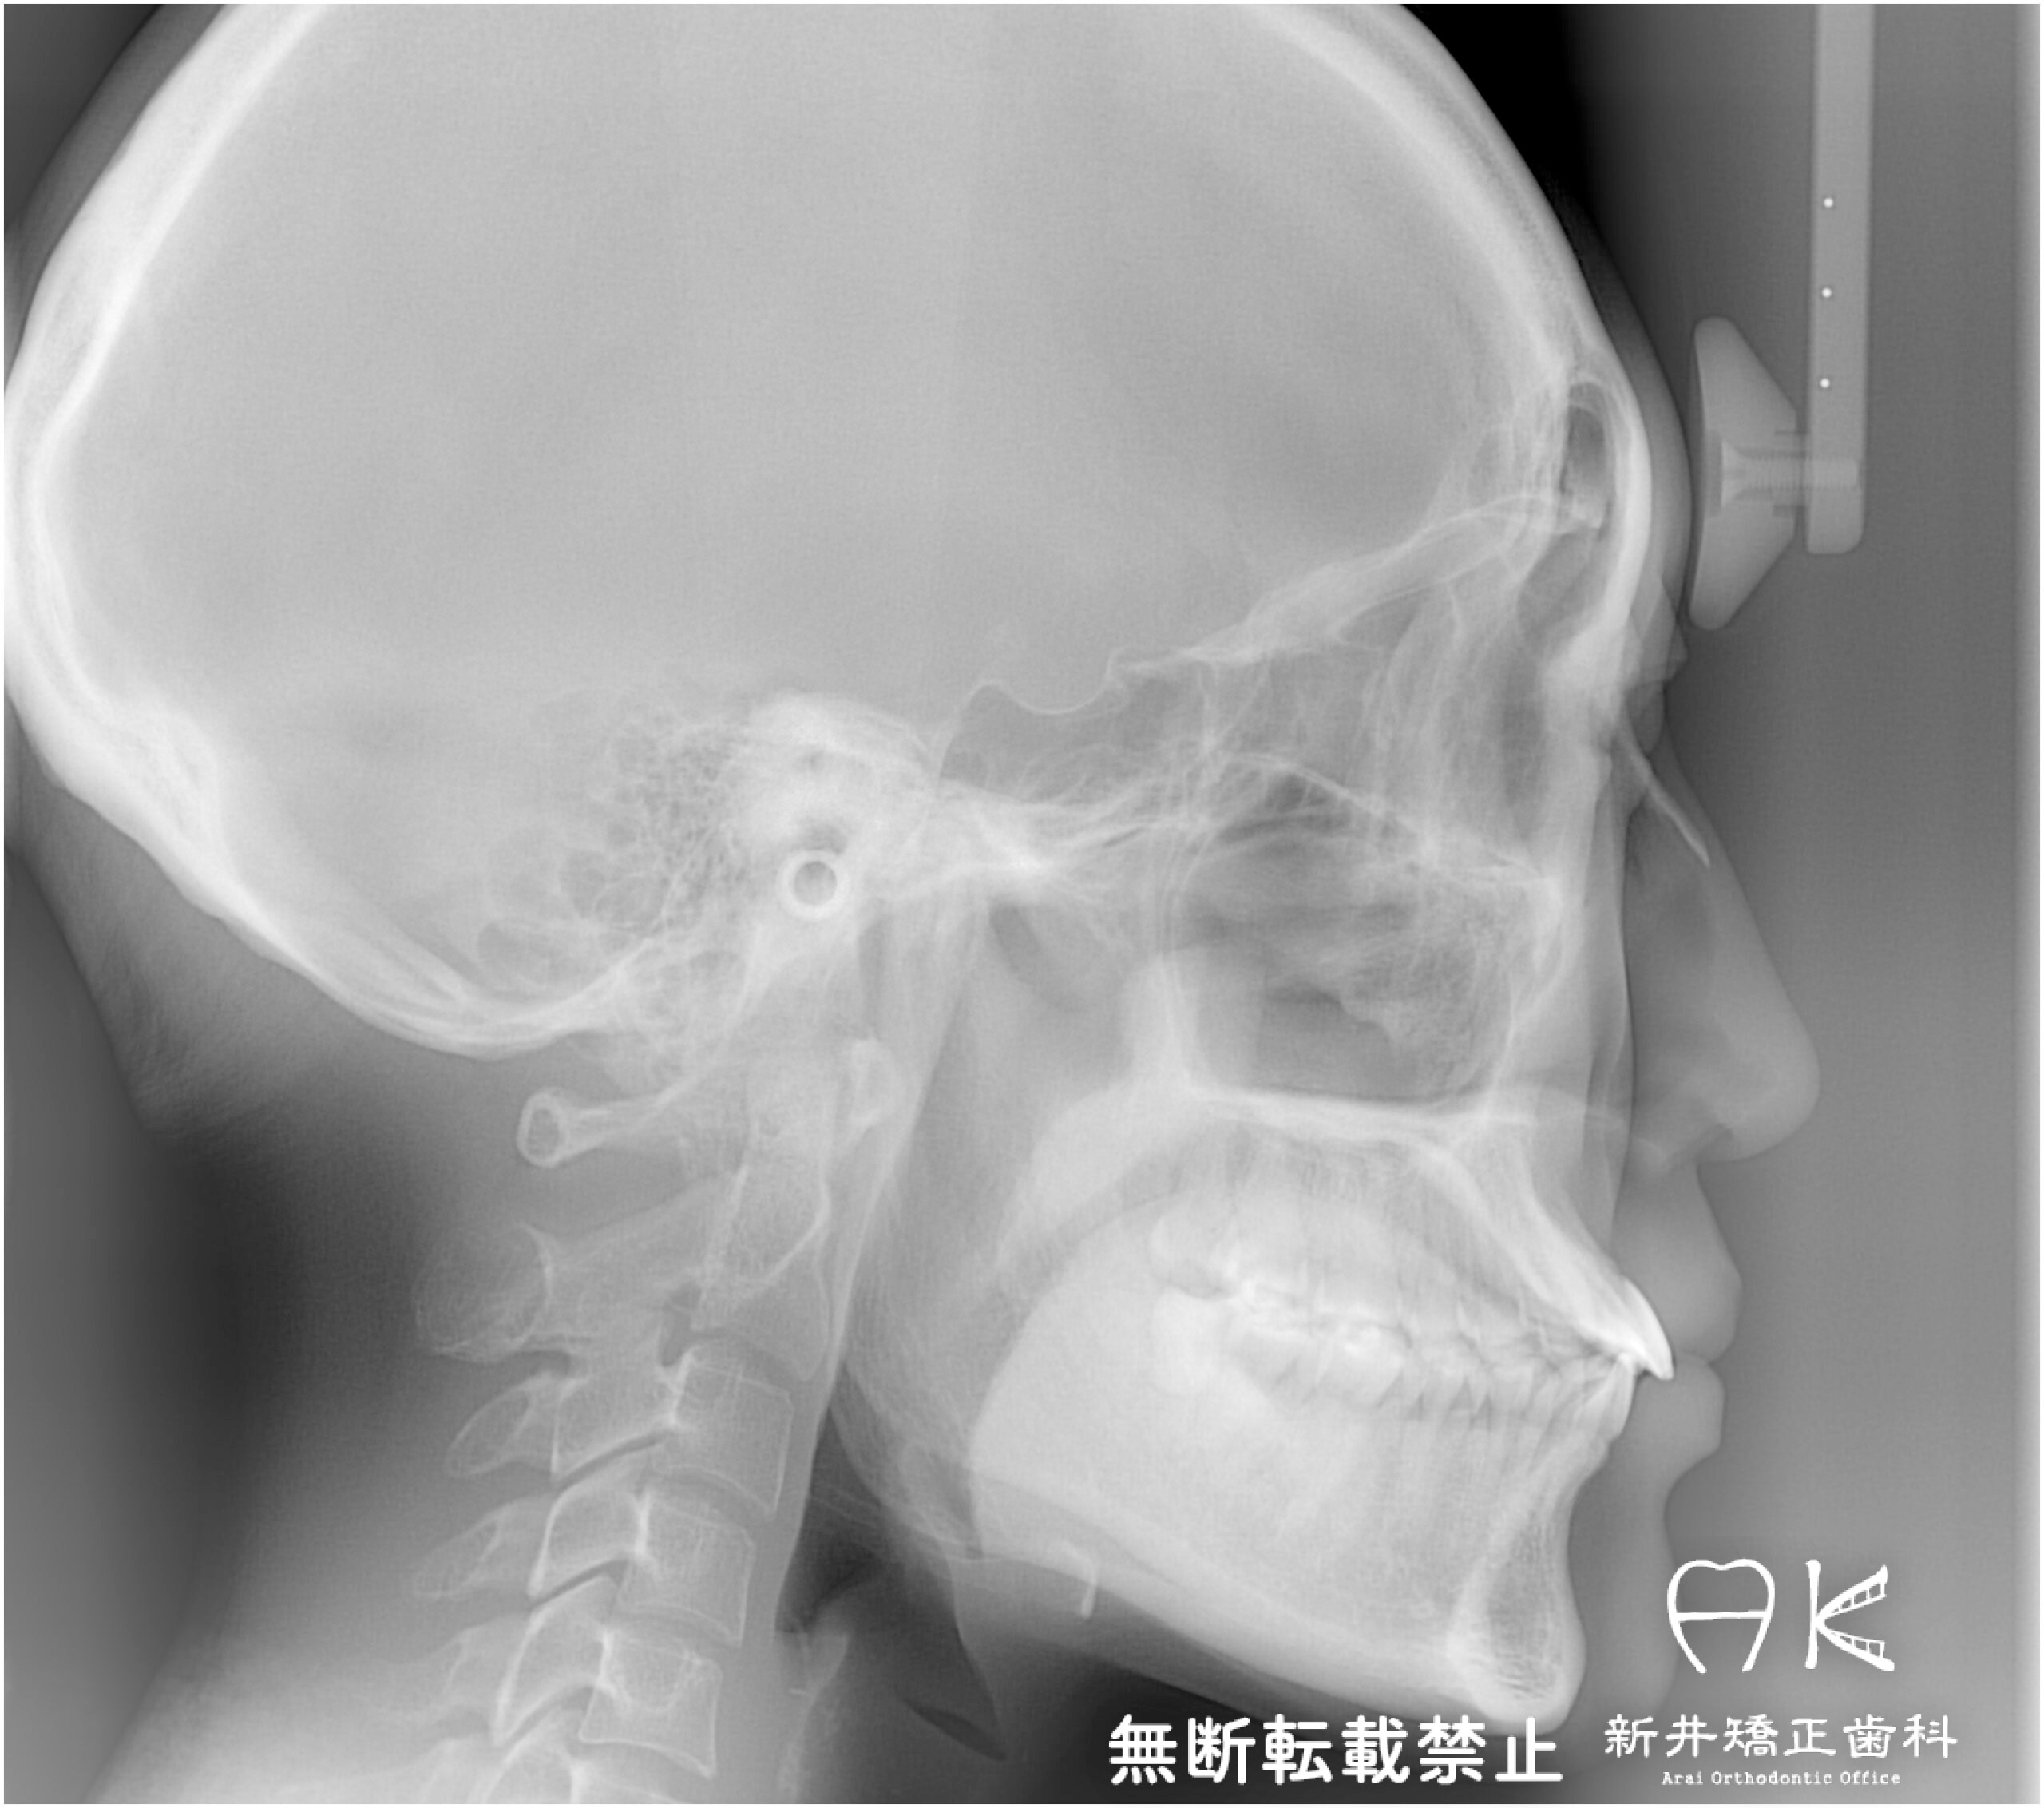

セファログラムのトレースの重ね合わせ(緑:治療前、赤:治療終了時)

| 治療前 | 上顎右側側切歯(2番目の歯)、上顎両側第二小臼歯(5番目の歯)、下顎右側中切歯(1番目の歯)、下顎左側第一大臼歯(6番目の歯)の合計5本の歯が先天的に欠損していた患者さんです。 先天欠損の他にも下顎骨の後退による骨格的な出っ歯の症状もありました。 矯正治療を開始する際に左上と左下のブリッジを切断し、上顎は隙間を全て閉じます。下顎左側第一大臼歯相当部はすでに歯槽骨が細くなっていたため、スペースを残して治療を進めていくこととしました。 |

| 治療後 | 前歯から奥歯まで全体的に緊密な咬み合わせになっています。 治療前はブリッジがあったため歯を抜いたように見えますが、元々歯の本数が少ないため、歯を抜くことなく現存する歯でかみ合わせを作りました。 出っ歯でもあり口元の突出感もありましたが、すっきりとした綺麗なイーラインになりました。 嚙むという機能性と見た目の審美性、どちらも患者さんにとって満足いく結果となりました。 |